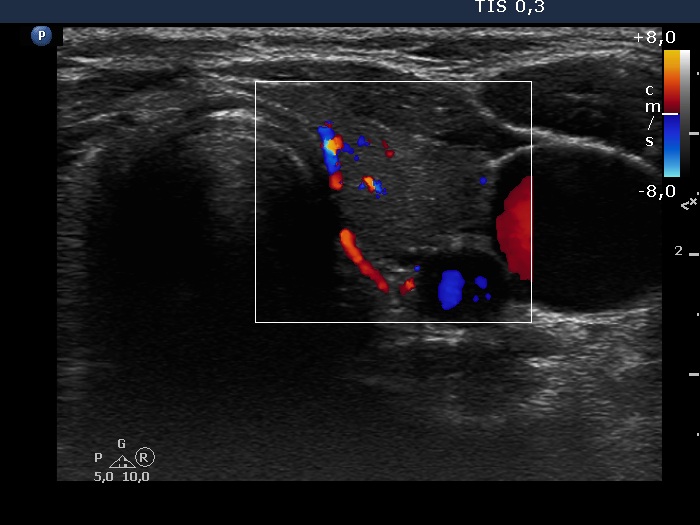

Consecutive patients with the final diagnosis of Hashimoto's thyroiditis - case 53 (101) (ultrasonographic picture 6)

Left lobe, transverse view, color Doppler mode. The vascularization is average.